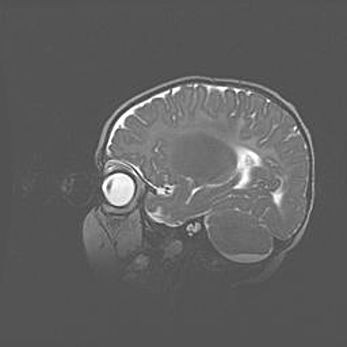

Церебральная ишемия II.

Возраст: 5 дней

Вес: 3400 г

Пол: женский

Окружность головы: 35 см

Срок гестации: 39 недель

Церебральная ишемия – это заболевание, характеризующееся недостаточностью (гипоксией) либо полным прекращением (аноксией) снабжения мозга кислородом по причине закупорки одного или нескольких сосудов. Это приводит к  что метаболическим расстройствам различной степени тяжести в тканях головного мозга, развитию коагуляционных некрозов и гибели нейронов.